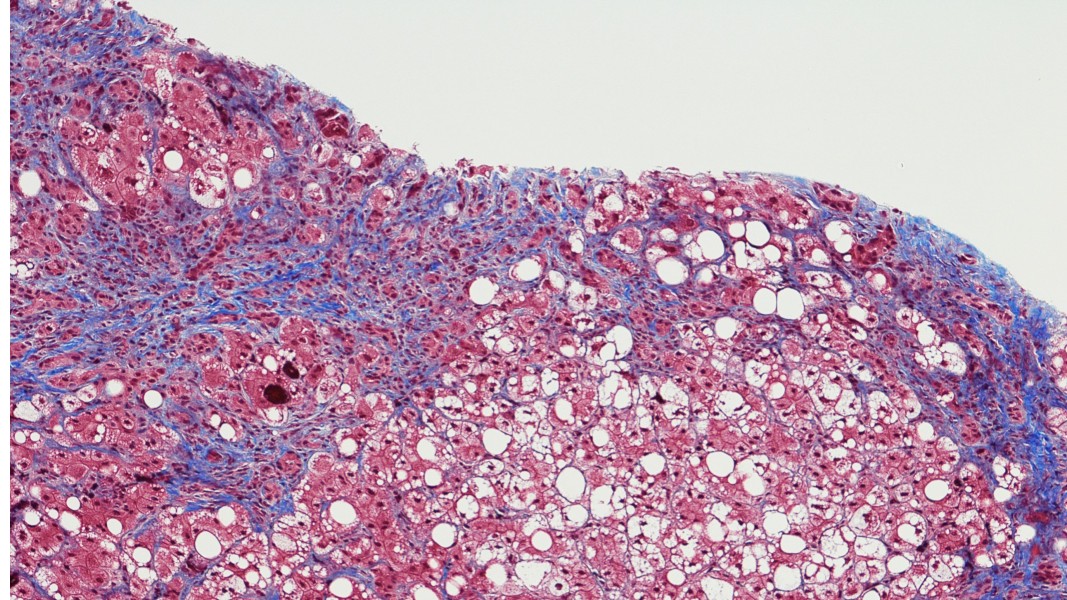

The process of adapting a high-quality FM yields better downstream pathology tools, with lower development time and cost, than building bespoke tools from scratch. For example, a pathology FM may be adapted variously to perform cell and nucleus segmentation at microscopic scale on immunohistochemistry (IHC) slides, or to perform histological subtyping at macro-scale for H&E slides. Developing high-quality FMs is particularly important and complex in pathology where there are many different kinds of tasks at different scales of the whole slide image (WSI) data including cell, tissue, and (whole) slide levels.

PathAI’s PLUTO was developed to enable this wide diversity of pathology tasks, and was trained using hundreds of millions of unlabeled image patches from about 160,000 WSIs across 30+ disease areas, numerous indications, stains, scanner types and magnification, and over 50 sources of data. To learn high-quality representations of the unlabeled training data, PathAI researchers designed a pathology-focused self-supervised training process using multi-scale, flexible deep vision transformer architectures with novel training objectives. Researchers then evaluated the quality of the resulting FM by adapting it to a wide diversity of pathology-specific tasks, and found that PathAI’s FM outperforms current state-of-the-art models on (whole) slide, cellular and subcellular tasks. Additionally, PathAI’s FM enables building AI-powered pathology tools at multiple scales and resolutions, and is significantly more compact than previously published models, driving massive reductions in training and inference costs, and enabling highly scalable data generation and product development.